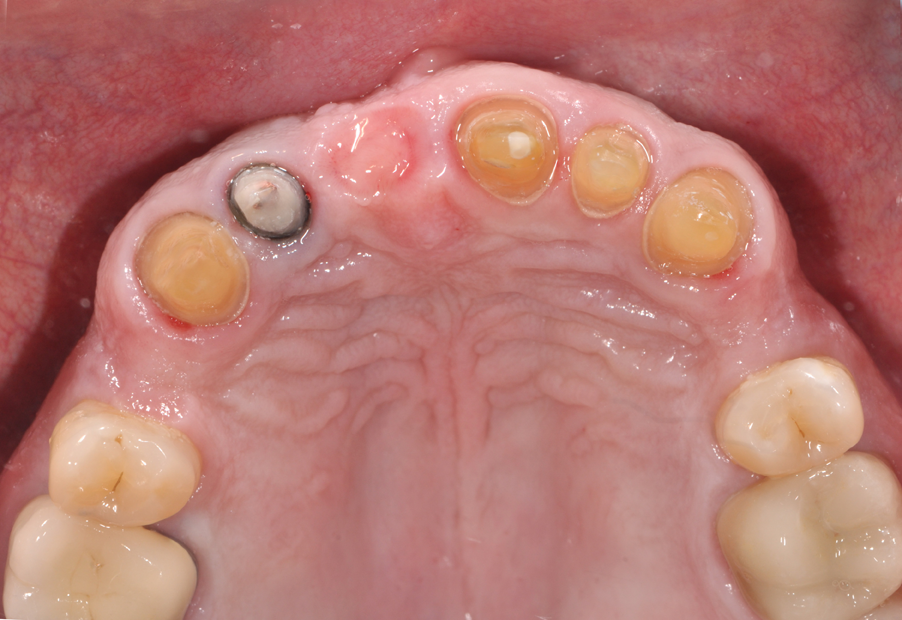

1. In Figure 1, we have an intraoral photograph of the patient with existing metal reinforced temporary bridge, which is planned for replacement with three implants and individual crowns. In Figure 2, we see another intraoral photograph after removing a PFM bridge, to reduce scatter in the DICOM image of the bone.

Fig. 1 Fig. 2